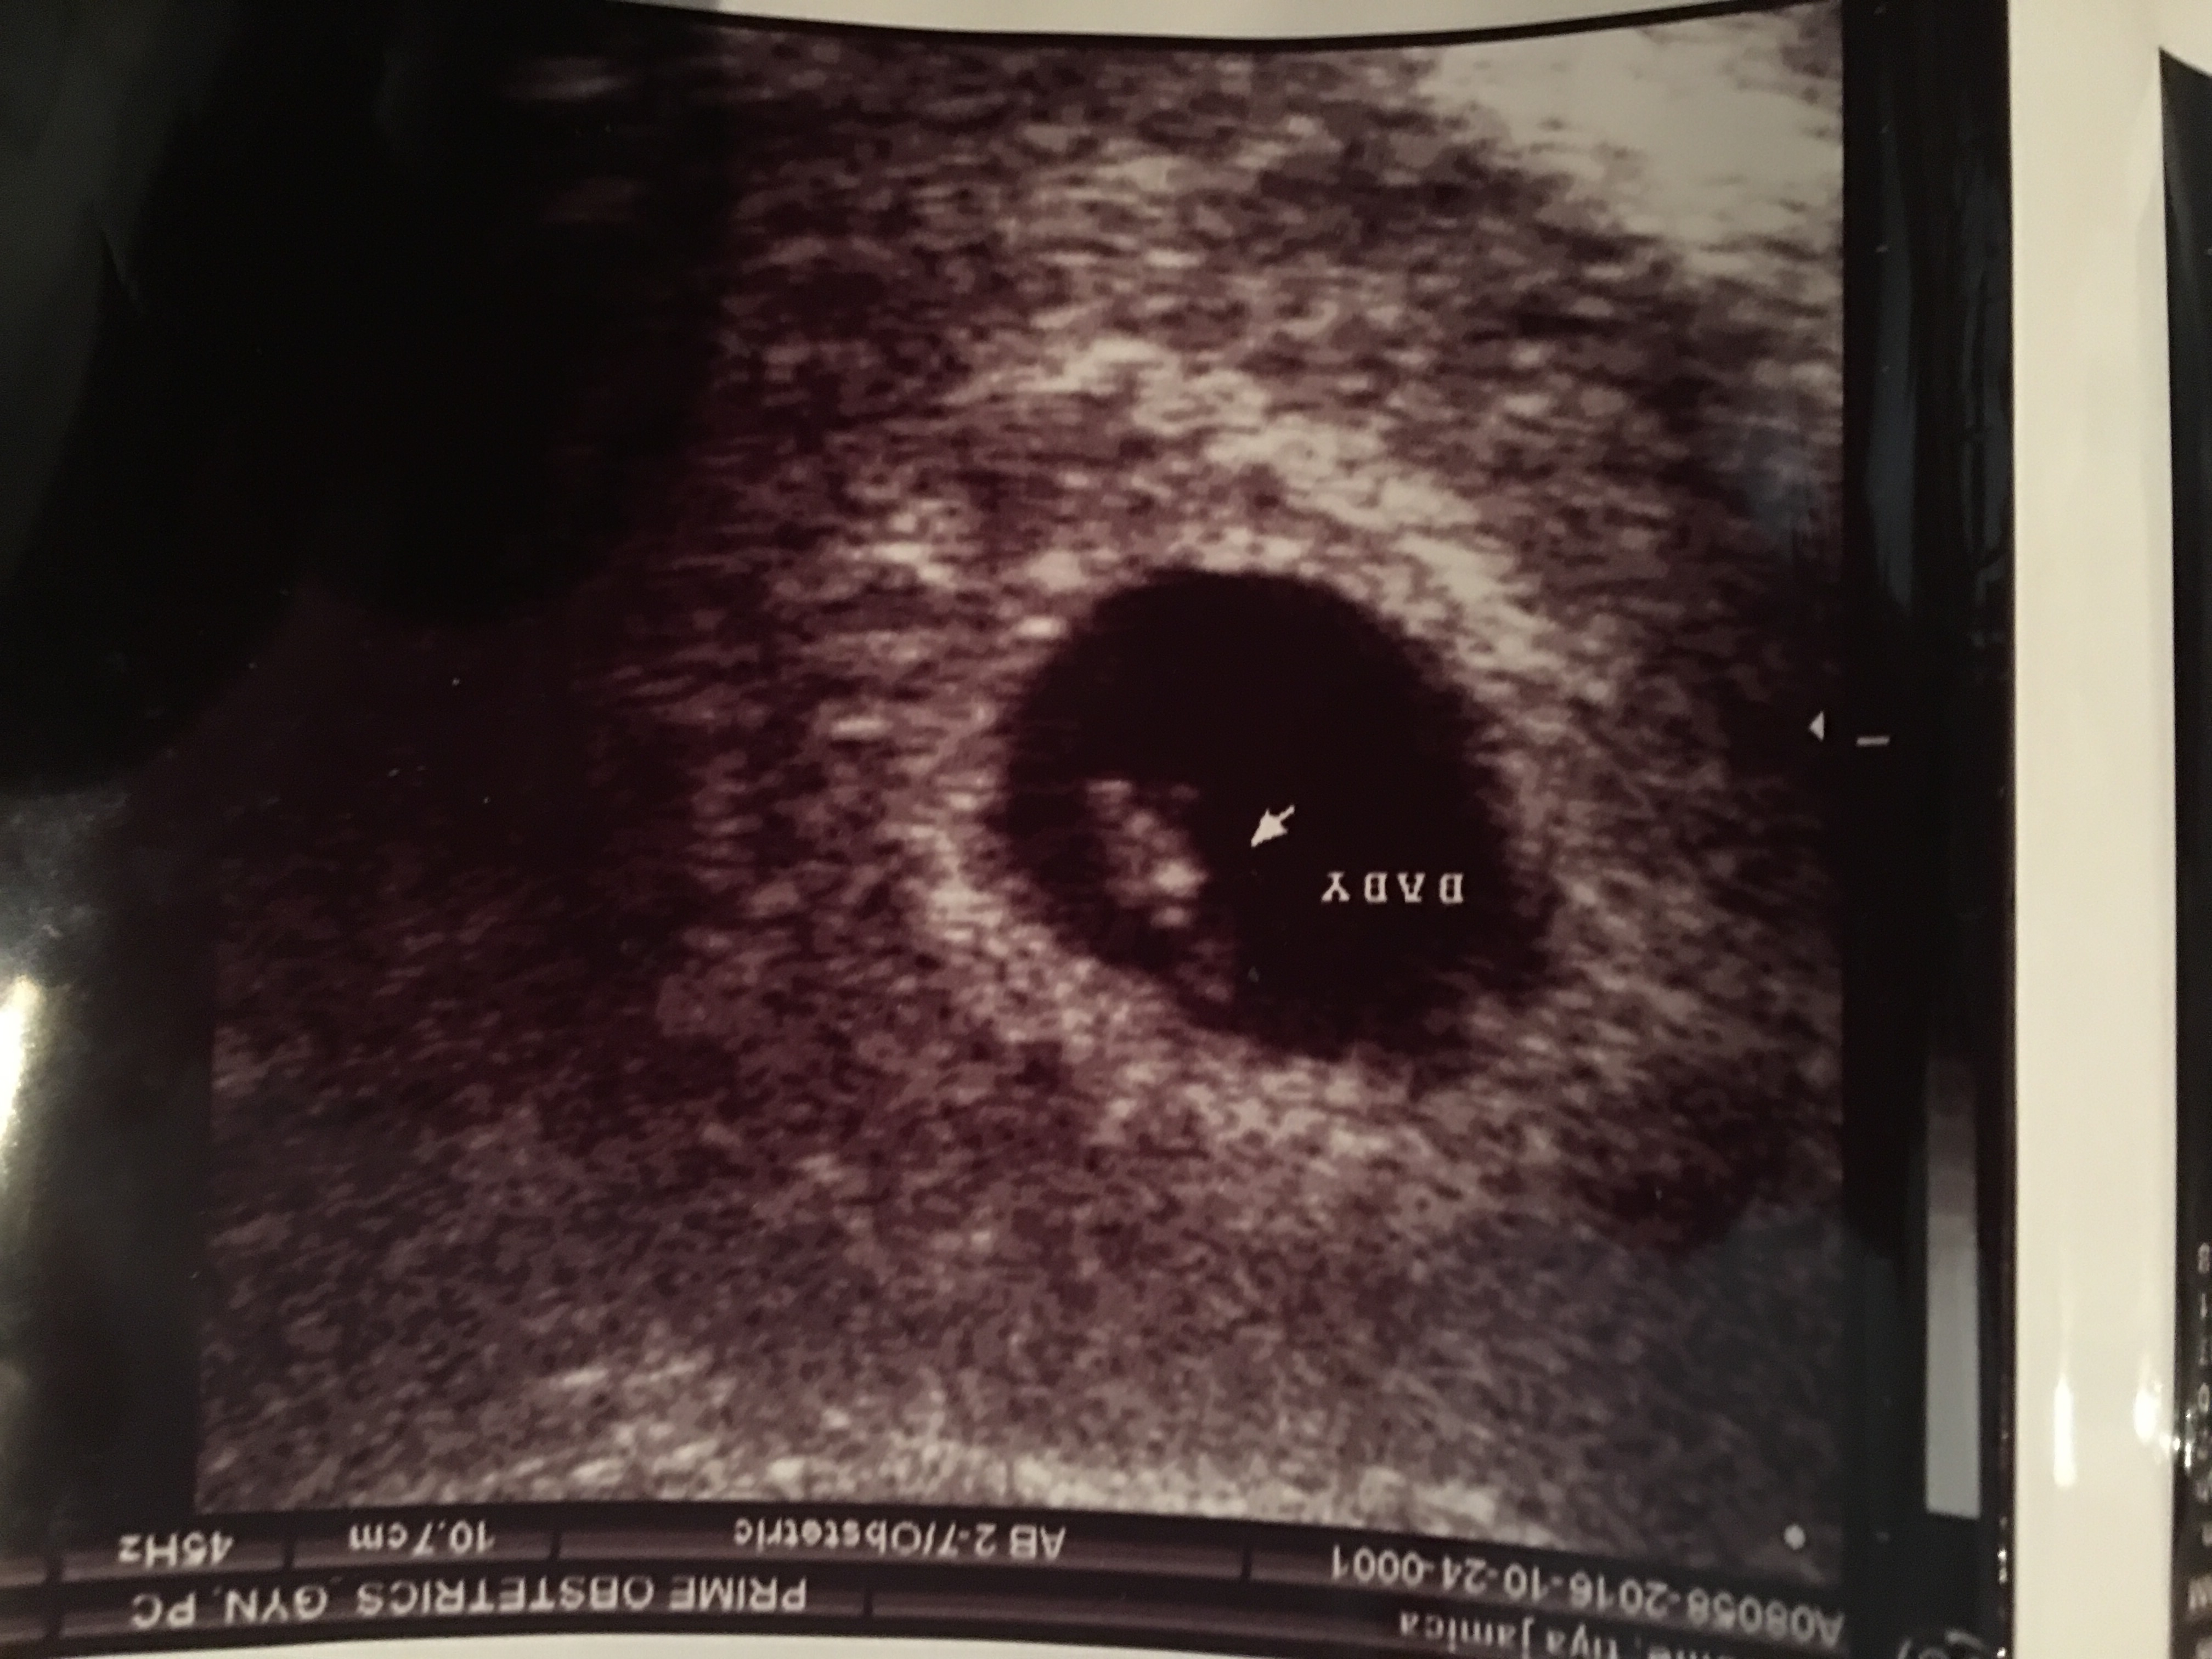

http://uploads.tapatalk-cdn.com/2016...5d046445e3.jpghttp://uploads.tapatalk-cdn.com/2016...5d046445e3.jpg Attachment 34144Attachment 34145